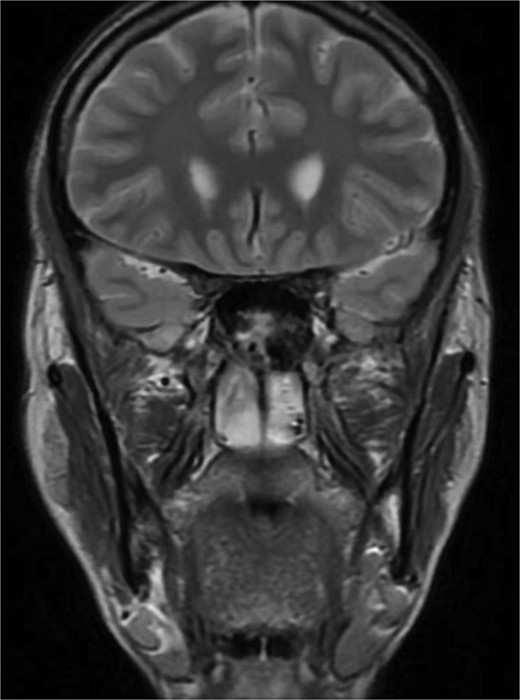

CT brain, coronal reconstruction shows bilateral near total opacification and expansion of the paranasal sinuses and nasal cavity. Invasion of the left cavernous sinus with encasement of cavernous segment of left ICA. Pituitary gland and optic chiasm displaced superiorly.

Patient presented to the emergency department with four days history of sever left side headache associated with nausea and vomiting, and nasal discharge with on\off nasal obstruction. Two days history of diplopia with lateral gaze of the left eye, with decrease the visual acuity. Ophthalmologic examination revealed left abducens nerve palsy. Other neurologic examinations were within normal. Endoscopic nasal examination revealed left multiple grade two nasal polyps occupying the middle meatus. Pre-operative brain computed tomography (CT) shows bilateral near total opacification and expansion of the paranasal sinuses and nasal cavity (Fig. 1). Additionally, there is evidence of invasion of the left cavernous sinus with encasement of cavernous segment of left internal carotid artery (ICA). Furthermore, pituitary gland and optic chiasm displaced superiorly. Magnetic resonance imaging revealed that the sphenoid sinus is expanded and bulging superiorly into the pituitary fossa causing displacement of pituitary gland and stalk without mass effect upon the optic chiasm (Fig. 2). It extends laterally causing effacement of the cavernous sinus and left Meckel’s cave. No evidence of intracranial extension. The patient underwent functional endoscopic sinus surgery with computer-assisted navigation system. Intraoperatively, sphenoid sinus was full of fungal mud and mucin (Fig. 3). The polyps were removed completely from the nasal cavities, fungal mud, and mucin were removed from the sinuses (Figs 4 and 5). Patient had dramatic improvement after surgery, the rhinosinusitis symptoms are resolved, the diplopia has been improved, and the paranasal sinuses were clear. The patient was discharged with topical corticosteroid and saline irrigations.